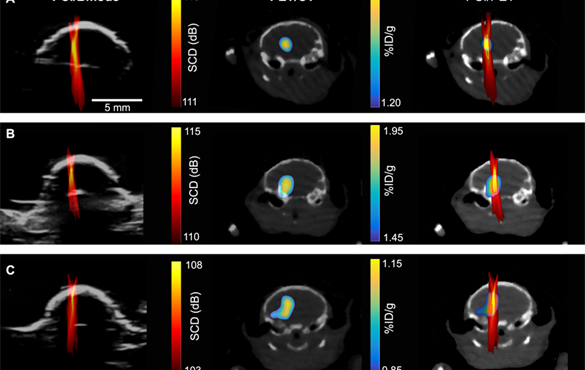

Researchers are one step closer to delivering precise amounts of medication to exact location, repurposing an existing imaging "painting" method. Cavitation images (left); PET images (middle); overlay of the two (right). (Courtesy: Hong Chen lab)

To determine where and how much of the drugs were being delivered, the researchers used nanoparticles tagged with radio labels to represent drug particles, then used positron emission tomography (PET) imaging to track their whereabouts and concentrations.

They could then create a detailed image, showing where the nanoparticles were going and in what concentrations.

To determine whether PCI could also accurately determine the amount of drugs at a certain location, they correlated a PCI image with a PET image (which they knew can quantify the concentration of radioactive agents).

“We found there’s pixel by pixel correlation between the ultrasound imaging and the PET imaging,” said Yaoheng Yang, the lead author of this study and a second-year PhD student in the Department of Biomedical Engineering. The PCI image, therefore, can be used to predict where a drug goes and how much drug is there. Hence, she called the new technique cavitation dose painting.